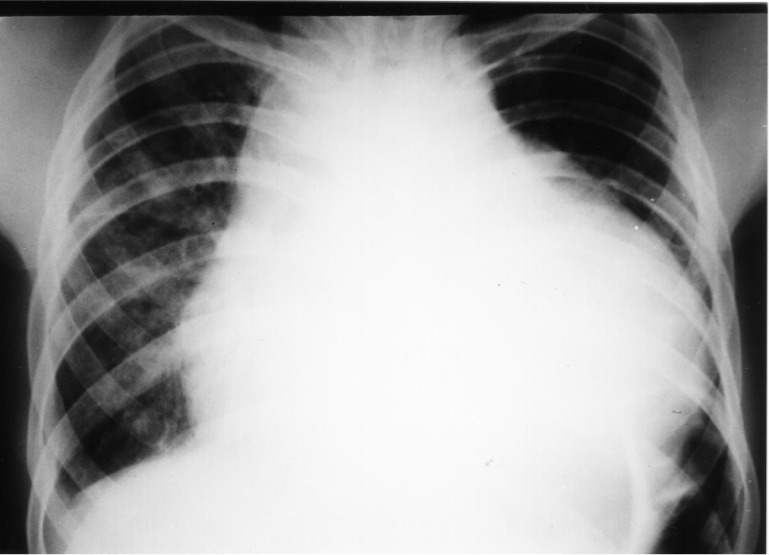

This middle-aged man, a sailor, was transferred to the hospital directly after his ship sailed into port. He had been ill for 2 months, with low-grade fever, weight loss of almost 8 kg, and shortness of breath upon exertion. His chest X-ray is shown below:

Along with the previously-described ECG changes, a diagnosis of cardiac tamponade (from massive pericardial effusion) was made, which was confirmed via urgent trans-thoracic echocardiography. Routine blood investigations performed at the emergency department revealed the following: